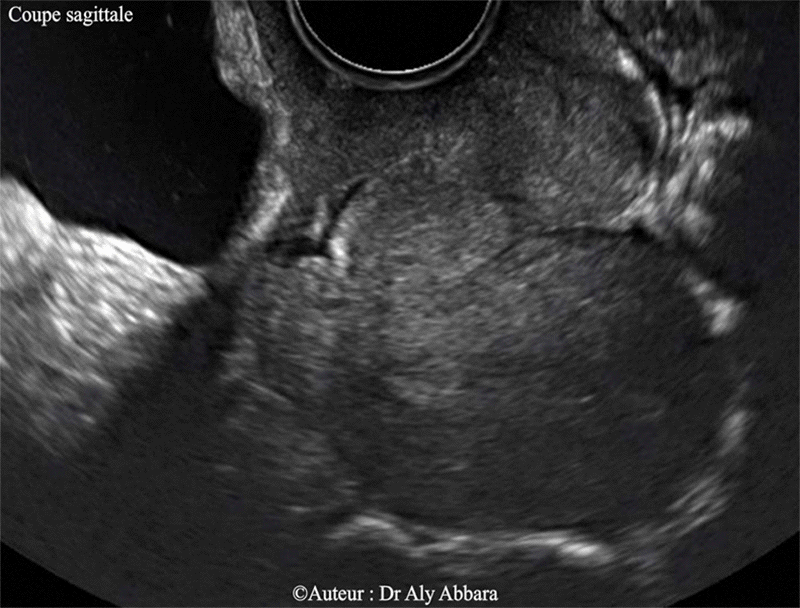

Utérus cicatriciel rétroversé rétrofléchi - Isthmocèle

Cicatrice d'une césarienne segmentaire transversale identifiable par l'échographie 2D. Il s'agit d'une cicatrice béante prenant, en coupe sagittale, l'aspect d'une zone anéchogène et profond, en forme d'une goutte d'eau (vessie pleine et selon la position de la coupe) ou d'un triangle (vessie vide) ; elle est situé dans la paroi antérieure de l'isthme utérin et communiquant avec la cavité utérine.

L'utérus est hyper-rétroversé, hyper-rétrofléchi ; cela explique la position du fond utérin qui se dérige vers le fond du pelvis.

En échographie 3D, mode "Triplan", cette zone béante peut être étudiée aussi transversalement et frontalement ; puis avec le mode "Omni view", la cicatrice peut être aussi analysée frontalement tout en étudiant la forme de la cavité utérine.